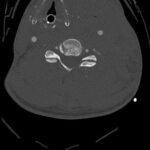

Penetrating wounds to the neck occur in 5-10% of trauma cases and are associated with very high mortality due to proximity to and involvement of vital structures. Emergent airway management and rapid diagnosis in these injuries are essential for life-saving treatment. This case study presents the case of a stab wound to the neck in an adult patient which elicited major concern for cardiovascular, neurological, and airway compromise. In such a high-risk trauma airway, this case shows the importance of keeping a wide differential and the value of expeditious management to prevent anoxic brain injury and stroke. The rapid diagnosis of a left common carotid artery transection and subsequent surgical repair were essential in this patient’s full neurological recovery.

Trauma, stab wound, neck hematoma, deviated trachea, carotid artery injury, carotid artery transection.